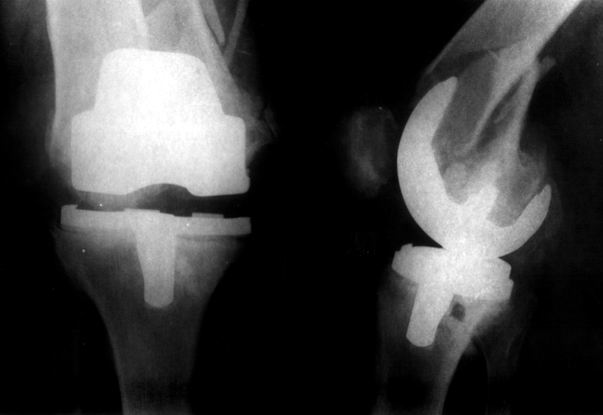

Видимо, самое "модное" на сегодня - малоинвазивный остеосинтез пластиной с угловой стабильностью. Распространенный вариант и закрытый интромедуллярный остеосинтез ретроградно. Хотя у нас было бы сделано антеградно - лешево и сердито, действительно малоинвазивно, в сустав не надо влезать. Нет риска прорезания порозной кости с миграцией в сустав, что возможно при ретроградном - гвоздь вводится через вырез в бедреннм компоненте, туда же может и вывалиться. А антеградный - упрется в протез. Как раз вчера заходил больной через полтора года после такой операции. Снимки в приложении.

Учитывая высокую вероятность уже имеющейся нестабильности тибиального компонента и развившуюся при травме нестабильность бедренного, имеет смысл удаление обоих компонентов, реэндопротезирование конструкцией, имеющей возможность интрамедуллярного закрепления на длинном стержне (NexGen LCCK (Zimmer), AGC (Biomet), RT-Solution (Plus Endoprosthetik) и т.п.), параллельно выполнить остеосинтез винтами, серкляжами, пластиной - что окажется лучше, решить во время операции.

Абсолютно согласен с А.Челноковым, есть определённый опыт применения пластин с угловой стабильностью. Здесь очень хорошо подойдёт LCP DF, она хорошо адаптироваана по мыщелкам, а открытым способом вообще

прекрасно получится. В области дистального фрагмента можно провести до 6 винтов в конвергенции поэтому можно получить абсолютную стабильность, несмотря на короткий отломок.